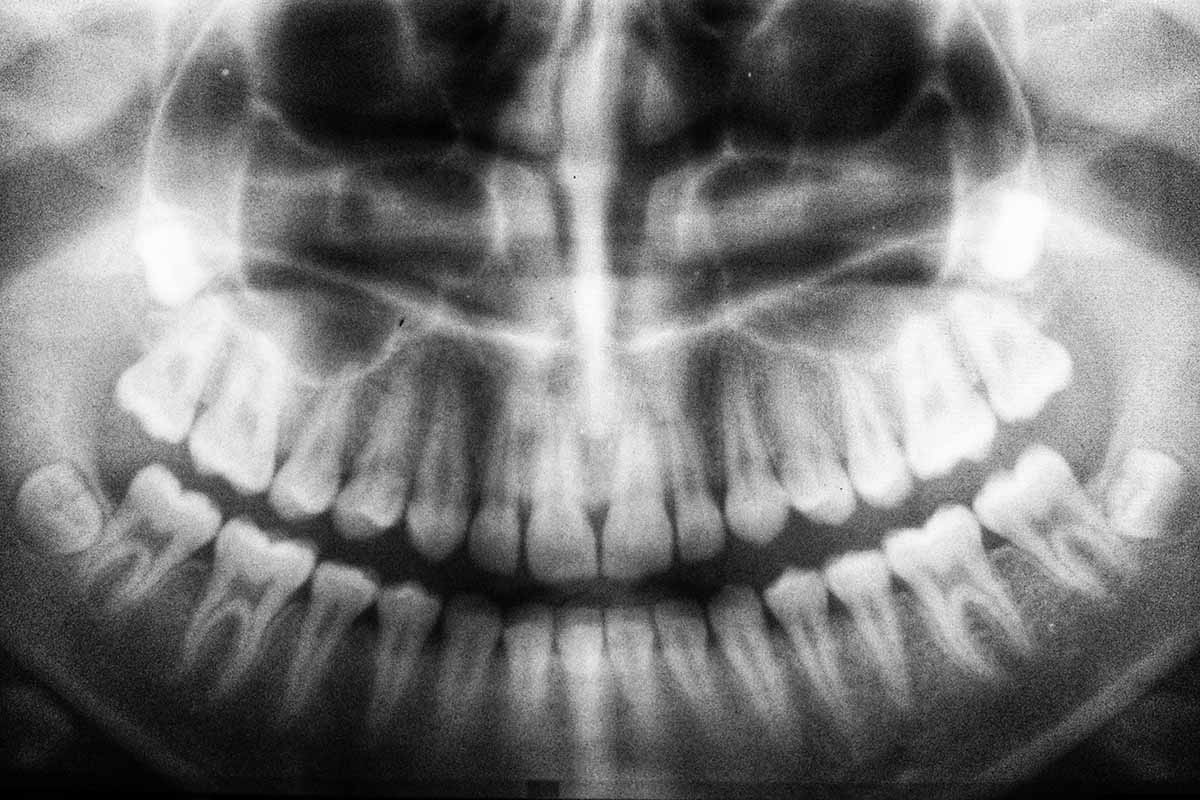

Fogászati problémák is állhatnak a fülzúgás kialakulása mögött, ezért fontos része a fülzúgás diagnosztizálásnak egy teljes fogászati állapotfelmérés.

Fiatal felnőttkorban különösen a bölcsességfog okozhat sok problémát. Egy állkapocsban maradt, félig, vagy egyáltalán nem kibújt fog, ami a fogsor felé nő, nem csak fájdalmat, fogíny gyulladást, ciszták kialakulását, hanem fülzúgást, fülfájást is okozhat.